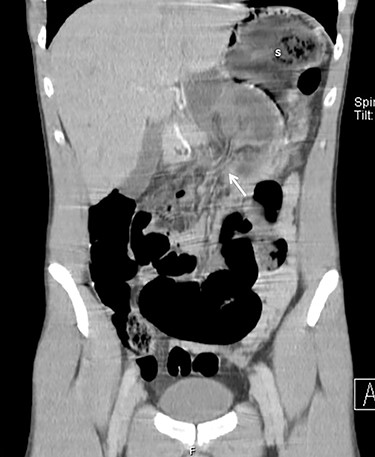

An exploratory laparotomy was then performed, which revealed herniation of jejunal loops through the gastrocolic ligament to the lesser sac, then protruding through a defect in the gastro-hepatic ligament (Figs 3 and 4). The initial ischemia of the bowel reverted after reduction and the omental defects were corrected. Of note was the frailty of the great omentum due to its very low adipose content.

Sagittal CT images with small bowel protruding the gastrocolic omentum (white arrow) to the lesser sac, pushing the stomach (s) upward.